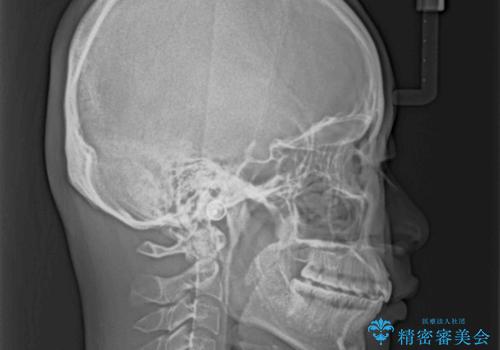

- 前歯の叢生と口元の閉じにくさを気にして来院された患者様です。

奥歯の咬み合わせを見ると、上顎が下顎に対して相対的に前方にありました。

口元の閉じにくさを改善するためには、上顎臼歯を後方に移動させた咬み合わせにする必要があります。

インビザライン単体で改善することも可能ですが、達成する可能性が高くないため、カリエールディスタライザーという補助装置を併用して、より確実性を上げることとしました。

奥歯の咬み合わせを改善しながら、並行してインビザラインで歯列を整えることとしました。

カリエールディスタライザーを併用したことで、確実かつ短期間で治療を終えることができました。